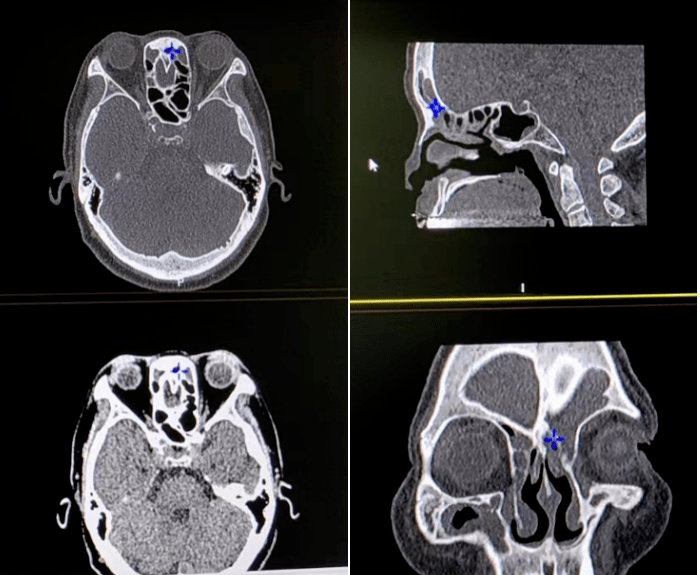

求助各位同仁这位5岁男孩鼻子中的灰白色肿物是肿瘤还

22岁男性上鼻窦疑似恶性肿瘤,但是做了全身ct没有转移,怎么判断早期

鼻窦ct发现左侧上颌窦肿瘤!鼻内镜发现左侧鼻腔出血性肿瘤!